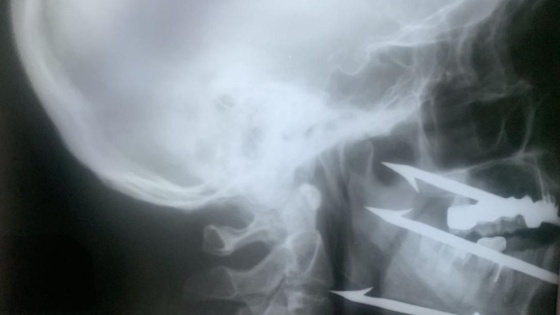

Мужчина случайно выстрелил из ружья, и трезубый гарпун вошел ему в лицо. Острие остановилось в миллиметре от сонной артерии. Любое смещение могло привести к гибели пациента.

Была сформирована объединенная бригада медиков. Операцию выполнили врач челюстно-лицевого отделения больницы № 1 Роман Стасюк и сосудистый хирург больницы № 25 Олег Виноградов. К слову, Стасюка в 2025 году признали лучшим хирургом региона.

Гарпун извлекли, медикам удалось сохранить сосуды и нервы.